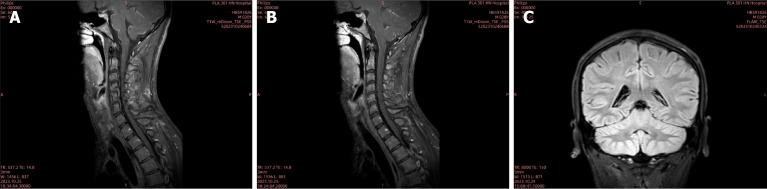

Case summary: A 20-year-old male developed persistent neck and back pain after consuming raw snail meat, followed by urinary retention and low fever. After admission, the patient was misdiagnosed as viral infection and Mycobacterium tuberculosis in central nervous system. After detection of Angiostrongylus cantonensis in blood and cerebrospinal fluid by metagenomics next generation sequencing, albendazole was administered with ceftriaxone and methylprednisolone treatment simultaneously. With effective antiparasitic treatment, the patient weaned from mechanical ventilation successfully and transferred out of intensive care unit for hyperbaric oxygen and rehabilitation treatment.